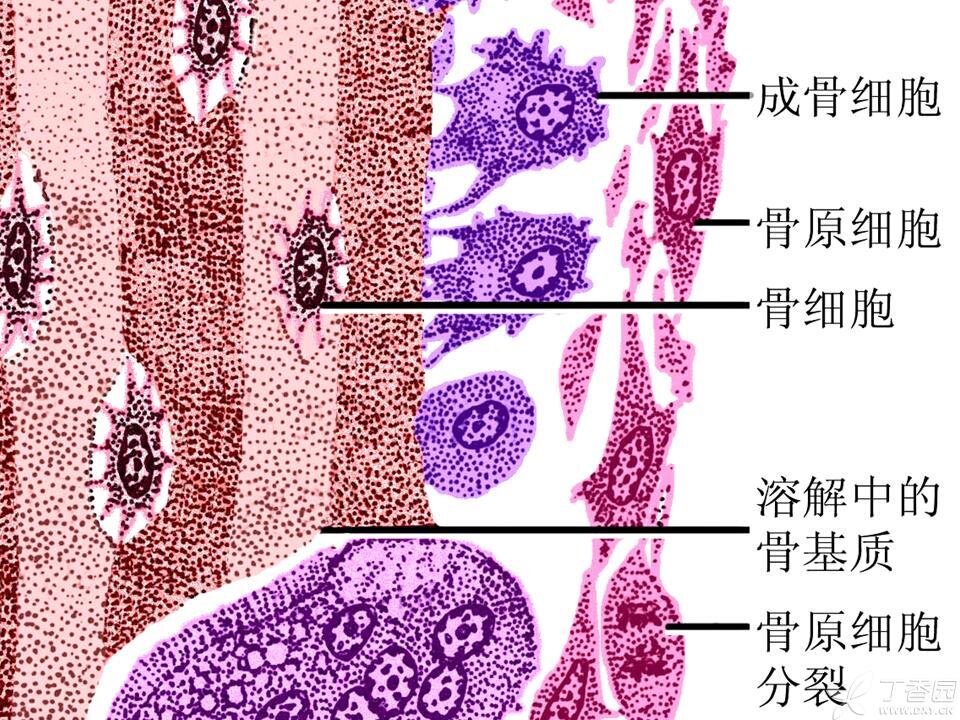

骨骼也和其他器官组织一样,包括细胞和基质。骨骼里的细胞分为骨原细胞,成骨细胞,骨细胞及破骨细胞。

骨骼里的各种细胞

破骨细胞的作用是吞噬吸收旧骨、病骨和死骨。骨原细胞是成骨细胞的预备队,随时可以转变为成骨细胞。成骨细胞的主要功能是分泌I型胶原蛋白,用来填充被破骨细胞“吃”掉骨质形成的“骨坑”,修复骨质。同时还成骨细胞还分泌骨钙素。

成骨细胞修复骨质的过程就像蚕宝宝吐丝一样,边吐丝边把自己包埋起来,一个成骨细胞3-4天分泌的胶原纤维就能把自己“淹没”,从而失去分泌功能,转变成了骨细胞。骨细胞负责骨骼的新陈代谢,吸收来自血液的氧气和营养物质,排泄二氧化碳和代谢产物。